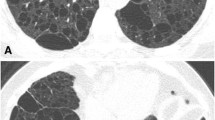

Imaging of LAM demonstrates the fairly unusual appearance of interstitial lung disease associated with hyperexpansion on chest radiographs (Fig. 8). Fine reticular opacities are seen in two-thirds of patients, and more than half of patients have large lung volumes. Cysts can be seen in about one-third of chest radiographs in LAM [99]. CT is more sensitive for LAM, and cysts are the predominant feature, seen in 100% of LAM patients. The cyst walls should be barely perceptible (but can be up to 2 mm thick) and are surrounded by normal lung [77]. The distribution is diffuse in 50% of patients, but 40% have apical sparing and the remainder have basal sparing [89]. Several investigators have reported lymphadenopathy associated with LAM [89, 99], but this was not a feature in a large series from the Armed Forces Institute of Pathology [99]. Small, noncalcified lung nodules have also been reported as a feature of LAM [88]. Pleural fluid collections are seen on CT imaging in 10–40% of LAM patients. If the fluid is chylous in nature, the attenuation should theoretically be less than zero Hounsfield units, but because they often contain increased protein content, this is often not the case [99]. LAM can also occur at extrapulmonary sites: LAM cells have been found in lymph nodes throughout the body, in the liver, and in the pancreas. Extrapulmonary LAM can be associated with chylous ascites and uterine leiomyomas [100].

LAM. a Chest radiograph demonstrates large lung volumes and diffuse fine reticular opacities throughout both lungs. Hyperexpansion in the setting of interstitial lung disease is unusual and should suggest the diagnosis of LAM, and therefore, at least consideration of TSC. b High-resolution chest CT image in a woman with TSC. Several smooth-wall cysts are present (black arrows) throughout the lungs. TSC/LAM is also associated with multifocal micronodular pneumocyte hyperplasia and a hamartomatous overgrowth of type 2 pneumocytes, and 2- to 5-mm nodules (white arrows) can often be found in these patients. c, d High-resolution chest CT with coned-down images in lung (c) and soft-tissue (d) windows shows a low-density (−5.3 HU) left pleural fluid collection, presumably a chylous effusion, a common complication of LAM